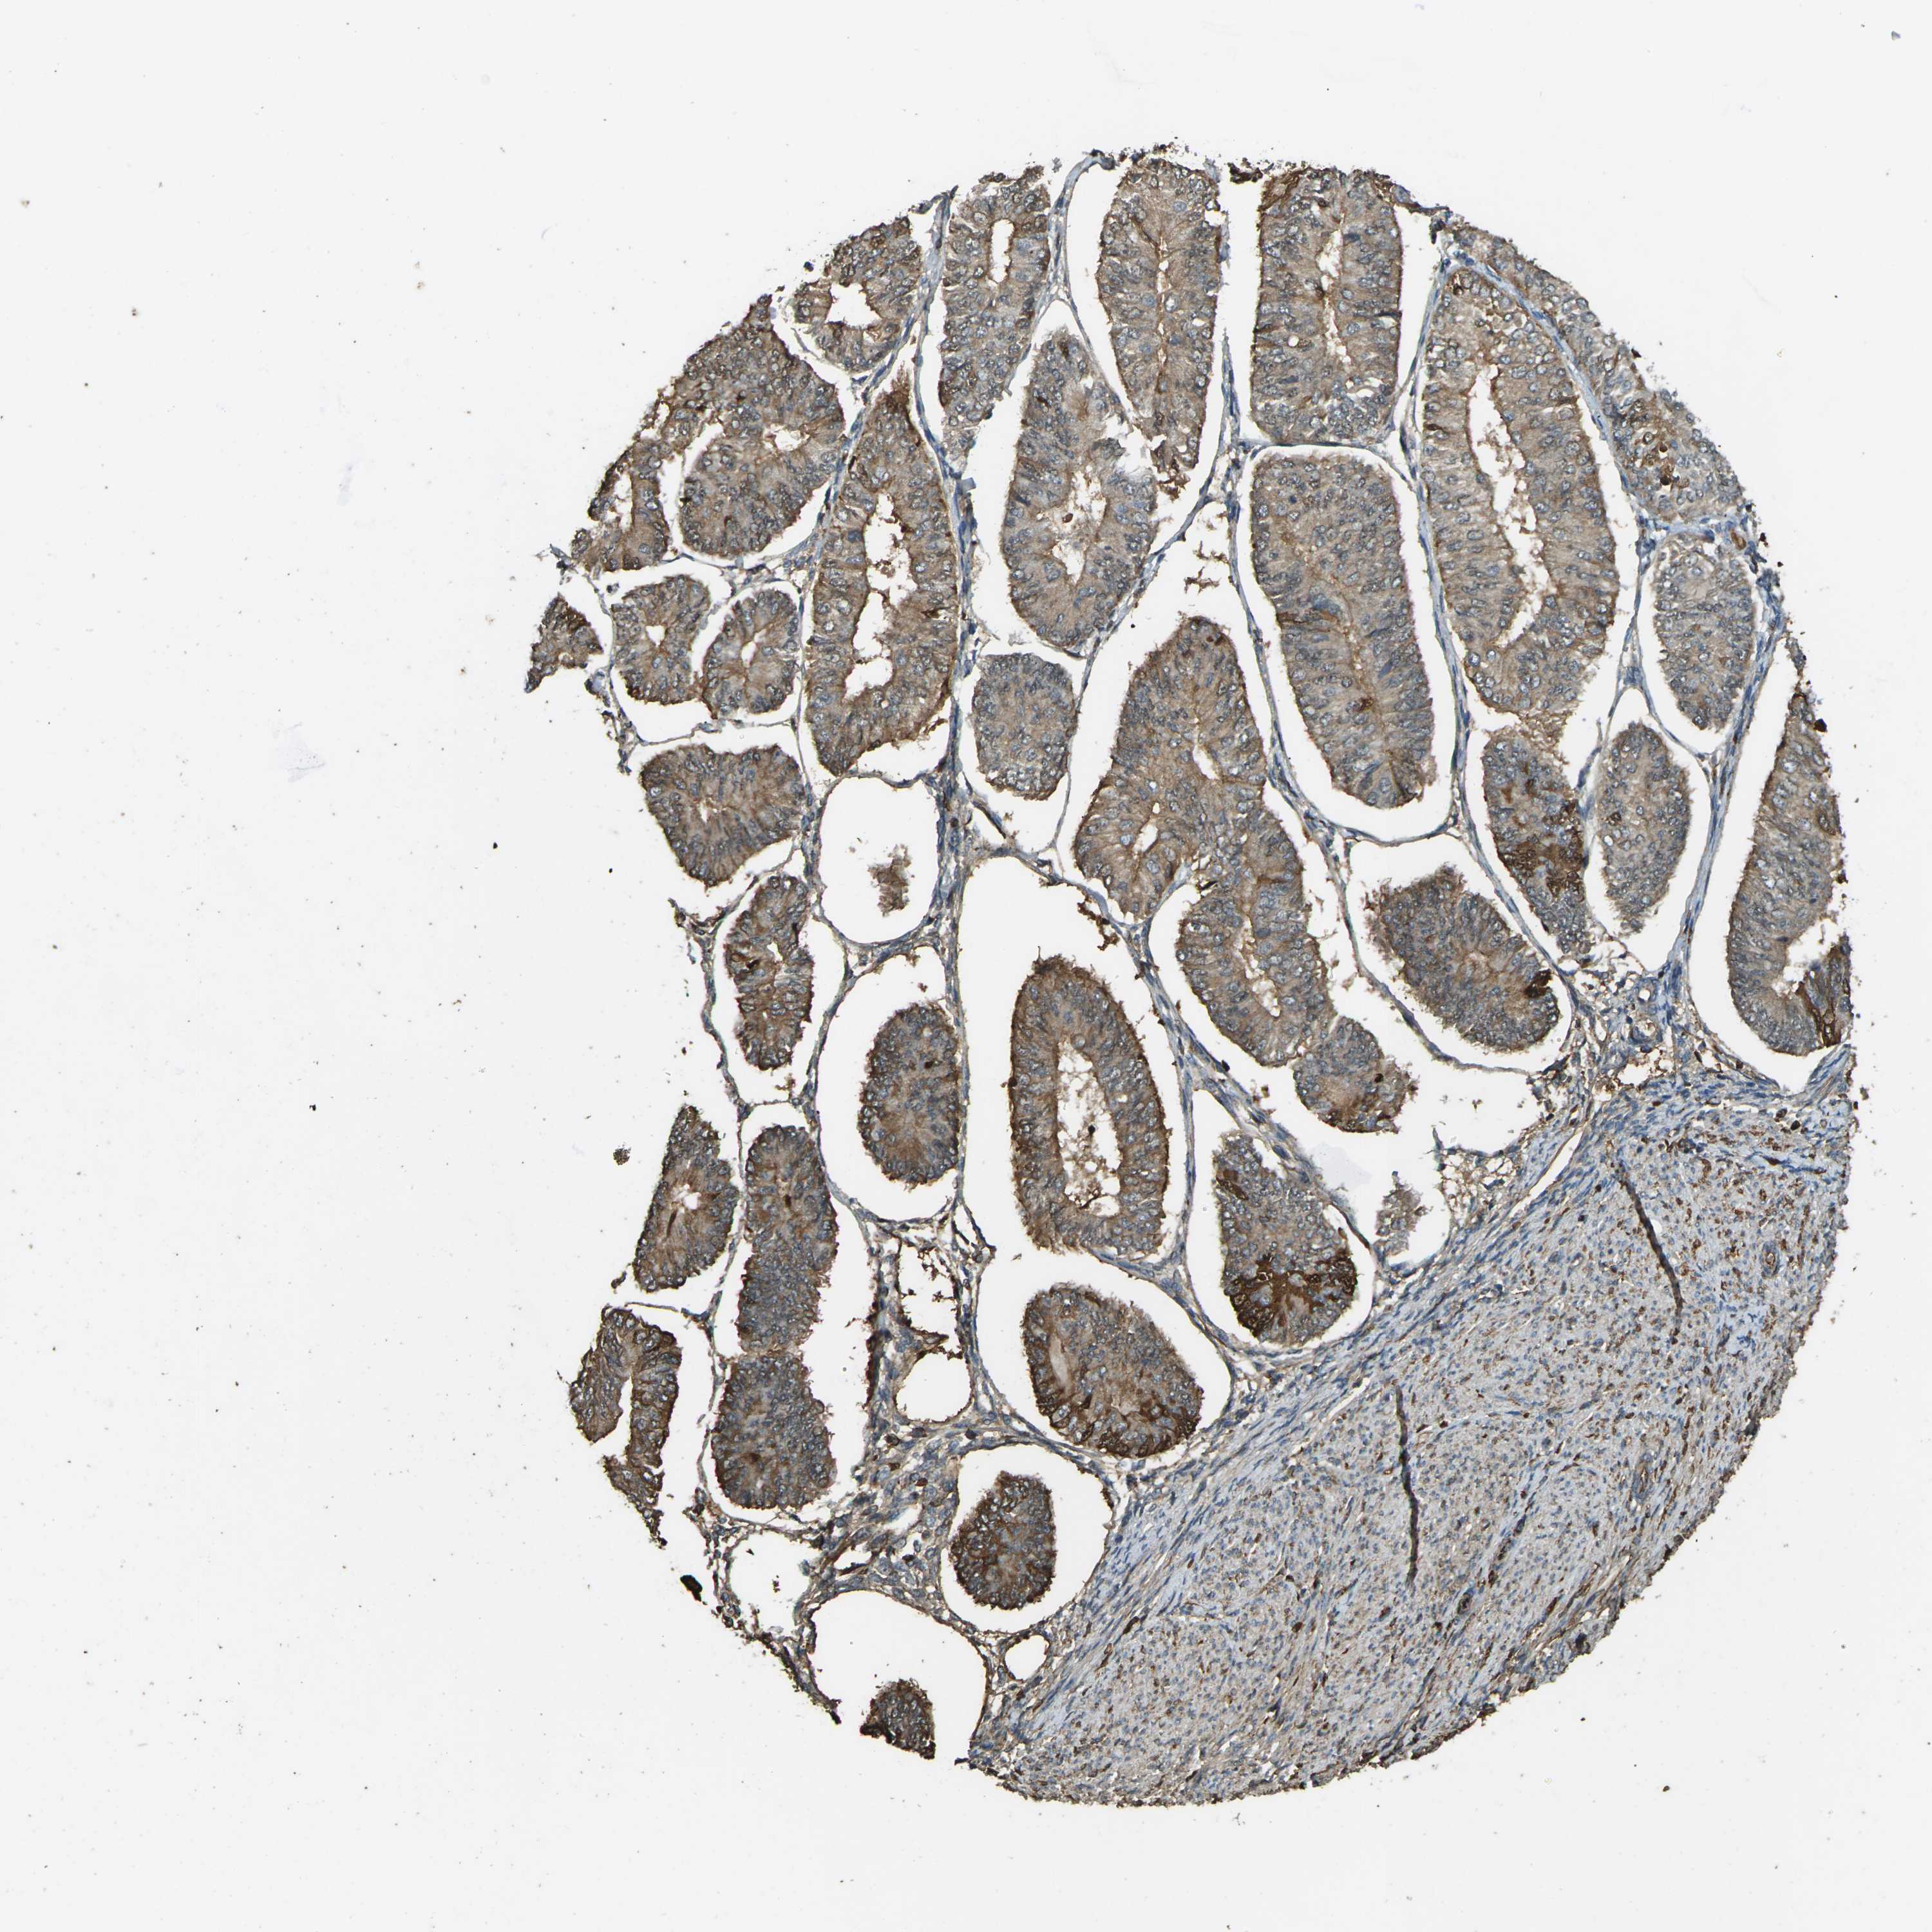

ENDOMETRIAL CANCER - Protein expressioni

A mouse-over function shows sample information and annotation data. Click on an image to view it in a full screen mode. Samples can be filtered based on level of antibody staining by selecting one or several of the following categories: high, medium, low and not detected. The assay and annotation is described here.

Note that samples used for immunohistochemistry by the Human Protein Atlas do not correspond to samples in the TCGA dataset.

Antibody stainingi

Antibody staining in the annotated cell types in the current human tissue is reported as not detected, low, medium, or high, based on conventional immunohistochemistry profiling in selected tissues. This score is based on the combination of the staining intensity and fraction of stained cells.

Each image is clickable and will lead to virtual microscopy that enables deeper exploration of all samples and also displays staining intensity scores, fraction scores and subcellular localization as well as patient and tissue information for each sample.

Antibody HPA026863

Antibody CAB011705

Staining

High

Medium

Low

Not detected

Intensity

Strong

Moderate

Weak

Negative

Quantity

>75%

75%-25%

<25%

None

Location

Nuclear

Cytoplasmic/membranous

Cytoplasmic/membranous,nuclear

Adenocarcinoma, NOS

Adenocarcinoma, metastatic, NOS